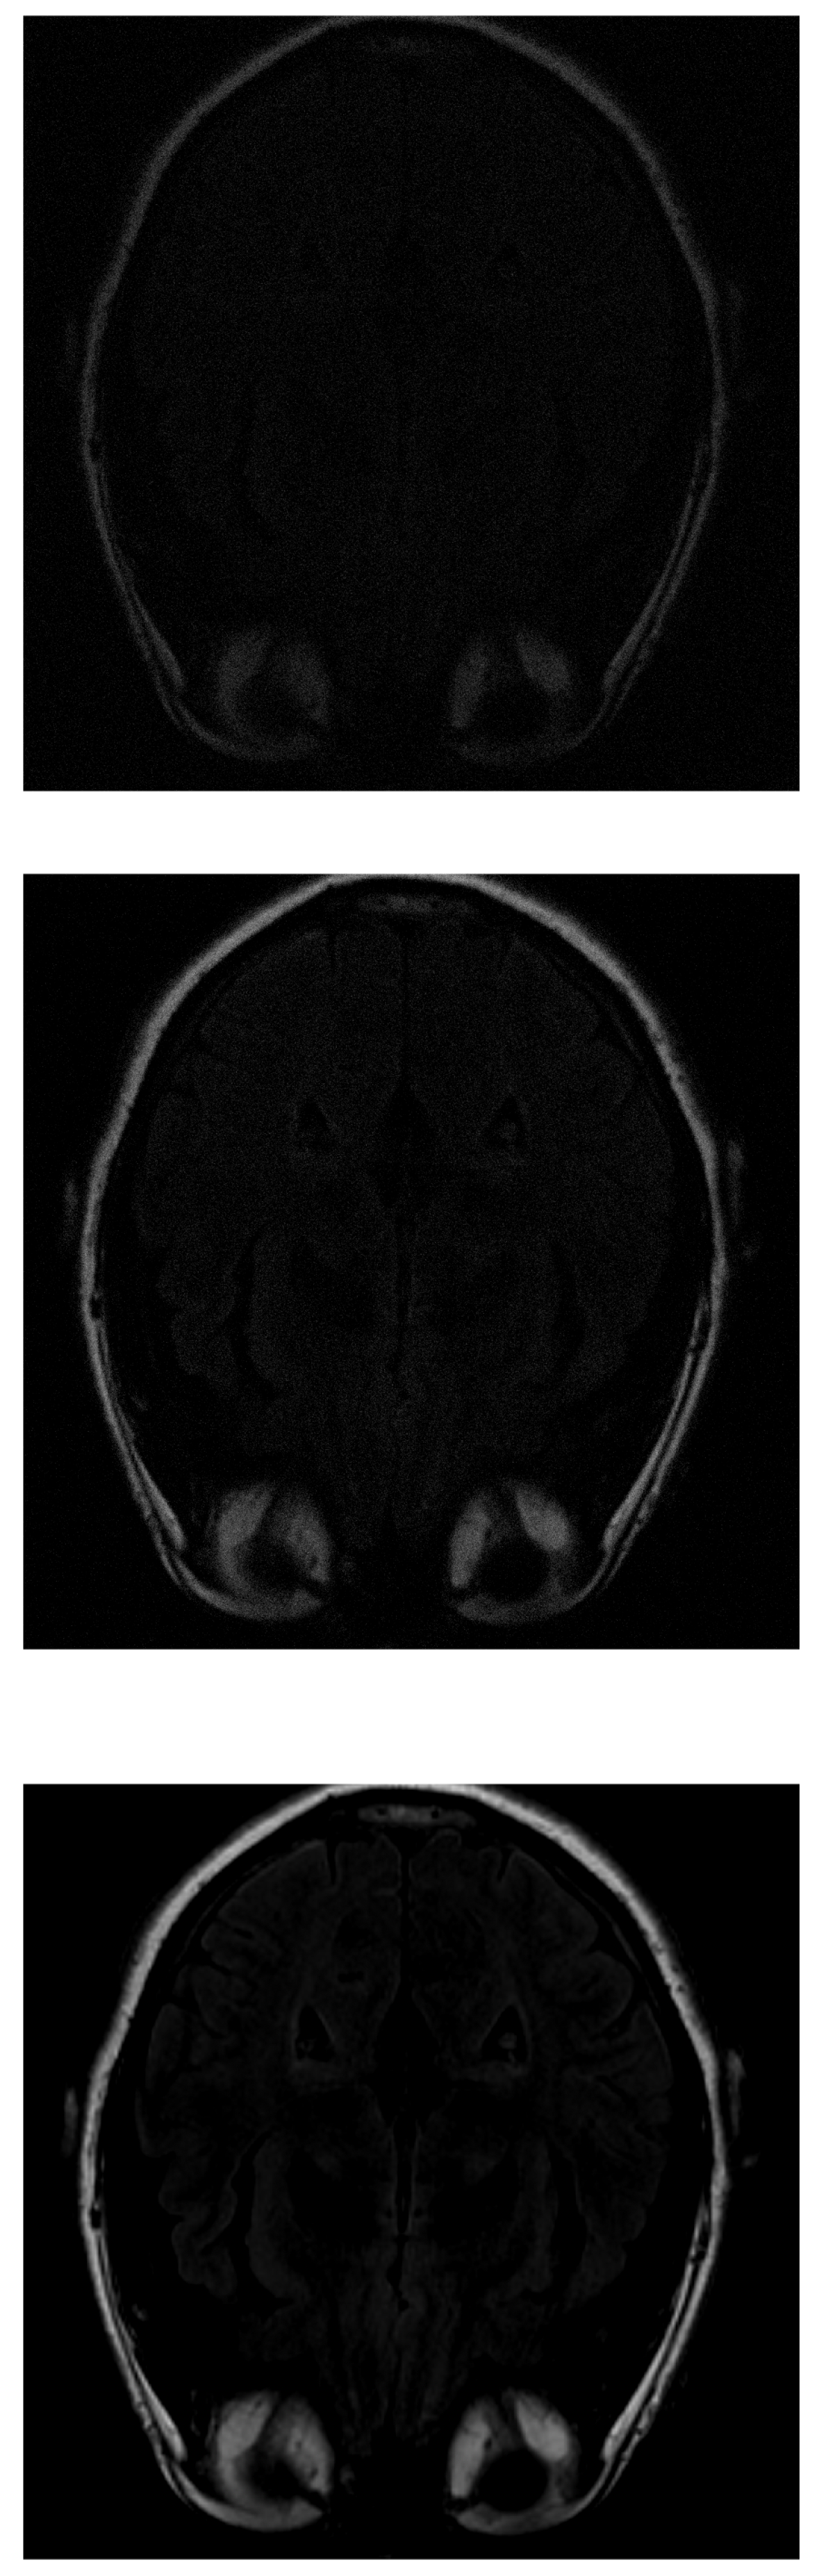

In the IRLS reconstruction, only the shape of the head and the orbits are detected in the first measurements, while the white matter is not distinguishable (Figure 5 top). When 70% of the data is available (Figure 5 middle), the white matter can be distinguished but with little intensity. When the intensity of the orbits increases, the effect of the artifact begins to be noticed. If the algorithm is run with all available data (Figure 5 bottom), the edge resolution is increased, but white matter signal intensity is lost. That makes their identification more difficult.

Figure 5.

Reconstruction of the image in Figure 3 using IRLS with (top), (middile) and (bottom) of taken measurements.